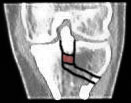

1. Das Problem, Bild links oben: Die zu hoch eingewachsene Eminenz (im Kniegelenk höchster Teil des Schienbeins, blau eingefärbt) verhindert die Streckung, weil sie am Oberschenkel anstösst, wenn das Bein gestreckt werden sollte (1).

2. Die Lösung: Weil an der Eminenz Bänder angewachsen sind, kann man das zu hoch stehende Fragment nicht einfach abhobeln - man muss es nach unten ziehen (2). Dafür muss aber zuerst Platz geschaffen werden...

3. Die Ausführung: Am Schienbein werden diverse Schnitte vollzogen. Im Bild rechts oben (3) ist der Schnitt von vorne sichtbar, im rechten unteren Bild (4) ein Schnitt von oben. Aus dem Schienbein ein Keil entfernt, sodass die zuerst von überschüssigen Knochenfragmenten befreite Eminenz gewissermassen nach vorne und unten ins Schienbein geklappt werden und mit drei Schrauben festgemacht (5) werden kann. In den unteren beiden Bildern ist auch schön sichtbar, dass die Eminenz nun wieder eine normalere Form hat.

Schön sichtbar sind auch die alten Löcher der im November 2001 entfernten Schrauben sowie in den Bildern rechts (gelbe Pfeile) eine alte Unterlagsscheibe, die während dem Sommer 2001 im Knochen festgewachsen war und im November nicht herausgefischt werden konnte (auf die Bildfragmente klicken, um eine grössere Fassung des Ausschnittes zu sehen).